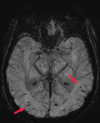

Neurodegenerative diseases are a devastating group of disorders that can be difficult to accurately diagnose. Although these disorders are difficult to manage owing to relatively limited treatment options, an early and correct diagnosis can help with managing symptoms and coping with the later stages of these disease processes. Both anatomic structural imaging and physiologic molecular imaging have evolved to a state in which these neurodegenerative processes can be identified relatively early with high accuracy. To determine the underlying disease, the radiologist should understand the different distributions and pathophysiologic processes involved. High-spatial-resolution MRI allows detection of subtle morphologic changes, as well as potential complications and alternate diagnoses, while molecular imaging allows visualization of altered function or abnormal increased or decreased concentration of disease-specific markers. These methodologies are complementary. Appropriate workup and interpretation of diagnostic studies require an integrated, multimodality, multidisciplinary approach. This article reviews the protocols and findings at MRI and nuclear medicine imaging, including with the use of flurodeoxyglucose, amyloid tracers, and dopaminergic transporter imaging (ioflupane). The pathophysiology of some of the major neurodegenerative processes and their clinical presentations are also reviewed; this information is critical to understand how these imaging modalities work, and it aids in the integration of clinical data to help synthesize a final diagnosis. Radiologists and nuclear medicine physicians aiming to include the evaluation of neurodegenerative diseases in their practice should be aware of and familiar with the multiple imaging modalities available and how using these modalities is essential in the multidisciplinary management of patients with neurodegenerative diseases.©RSNA, 2020.